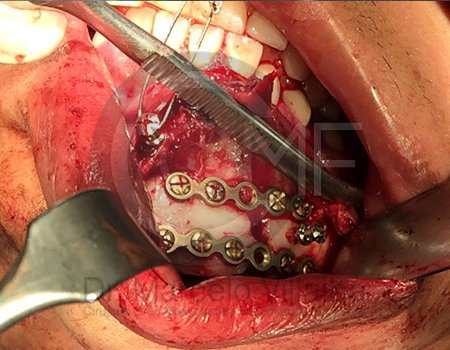

La Cirugía Oral y Maxilofacial es una de las especialidades odontológicas que brinda la posibilidad de ofrecer soluciones medicas y quirúrgicas a diferentes problemas de salud, entre los que se encuentran los defectos congénitos como el labio y paladar fisurados, las disarmonias del desarrollo facial, los traumatismos y lesiones patológicas de la región oral y maxilofacial por mencionar algunos; utilizando distintos procedimientos como la Cirugía Ortognática, la Reconstrucción mediante toma y colocación de injertos, distractores osteogénicos, regeneración tisular, implantes, etc.

Contenido Sensible y Gráfico

Si usted no pertenece al área de la salud, las imágenes pueden ser muy explícitas.